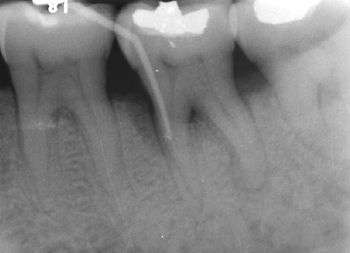

Furcation defect

In dentistry, a furcation defect is bone loss, usually a result of periodontal disease, affecting the base of the root trunk of a tooth where two or more roots meet (bifurcation or trifurcation). The extent and configuration of the defect are factors in both diagnosis and treatment planning.[1]

The distance between the cementoenamel junction (CEJ) and the furcation entrance is called the root trunk length. This distance plays an important role in furcation defects because the deeper the furcation entrance is within the bone, the more bone loss necessary before the furcation becomes exposed.

For mandibular first molars, the mean root trunk length is 3 mm on the buccal aspect and 4 mm on the lingual aspect.[2] The root trunk lengths for mandibular second and third molars are either the same or slightly greater than for first molars, although the roots may be fused.